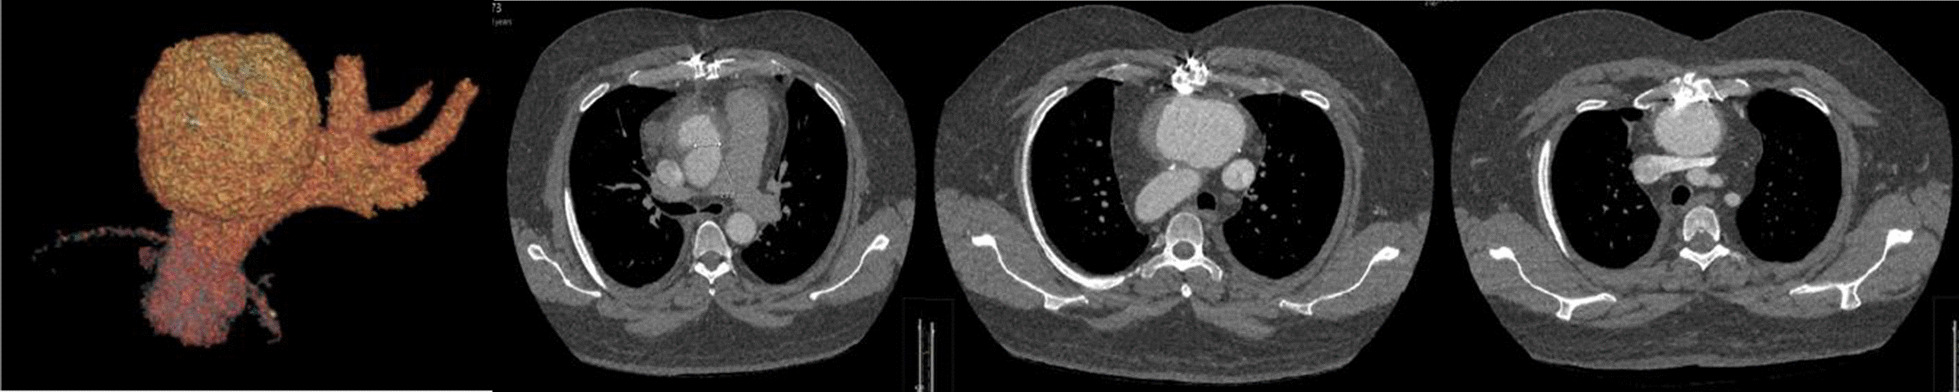

Fig. 1.

Pre-operative imaging

In August of 2021, the patient represented with rapidly deteriorating vision in his right eye and was transferred to a tertiary ophthalmology unit. Corneal scrapings demonstrated Aspergillus Fumigatus and Saccharomyces Cerevisiae and a CT thorax abdomen and pelvis confirmed disseminated fungal infection and fungal endophthalmitis. A 74 mm × 76 mm saccular pseudoaneurysm was found arising from the mid anterior ascending aorta, with a wide 24 × 21 mm diameter orifice and no neck. The pseudoaneurysm was in close apposition to the manubrium and proximal sternal body. The features were in keeping with a large fungating mycotic pseudoaneurysm arising from the previous aortic suture line and aspergillus infection was strongly suspected. The patient was commenced on anti-mycotic therapy and transferred to a quaternary aortovascular centre for re-sternotomy and repair of the ascending aortic pseudoaneurysm.